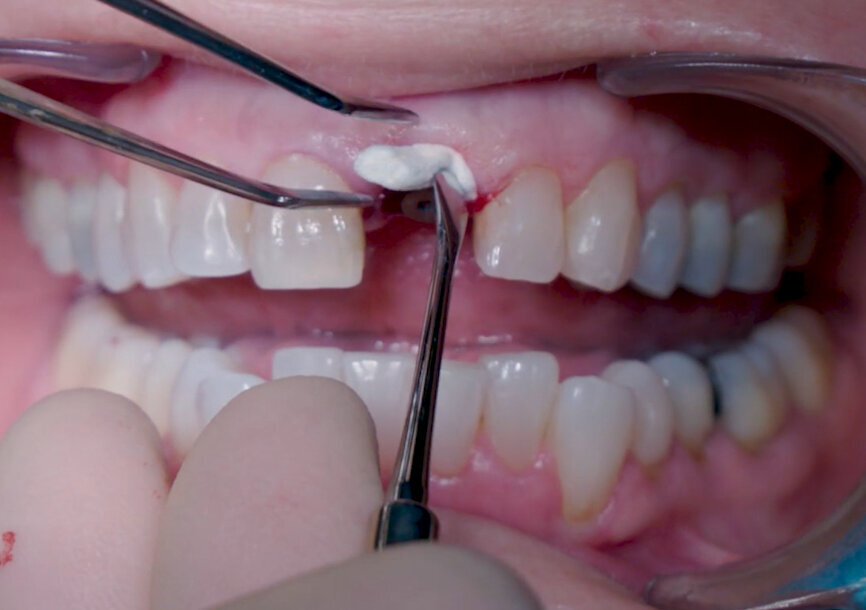

Fig. 22: Fitting assessment of provisional tooth shell.

Fig. 26: Temporary provisional tooth shell after pick-up impression taking and emergence profile creation.

A Ø 4 mm temporary abutment with a gingival height of 2.5 mm was placed on to the implant, and it showed no crestal bone interference, allowing for appropriate creation of the emergence profile (Fig. 19). The tooth shell, which was designed and milled in PMMA prior to the procedure (Figs. 20 & 21), was tested to ensure that the contours and retention wings were appropriate and caused no interference (Figs. 22 & 23). The palatal side, including a small portion of the incisal edge, was opened in order to allow screw channel access (Figs. 24 & 25). The lateral wings of the tooth shell allow the provisional temporary crown to stay immobile during the pick-up procedure, which is a common problem clinicians face when performing the immediate pick-up technique. The tooth shell was bonded to the temporary abutment using flowable light-polymerising composite, and a slim emergence profile was created to the subgingival portion using the same material (Fig. 26). At this point, the retention wings were removed. With no compression to the soft tissue, the provisional crown was seated and the incisal edge adjusted to ensure that the antagonist tooth was not touching it in excursive movements. The provisional crown was torqued to 25 Ncm, and the screw access hole properly closed and polished (Fig. 27). The patient was seen seven days later for postoperative and periapical radiographic control (Figs. 28 & 29).